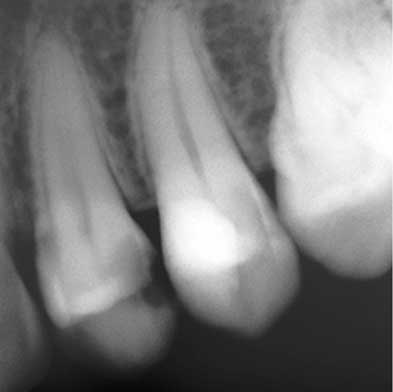

Endodoncia

Dra. Carmen Feito Bárcena